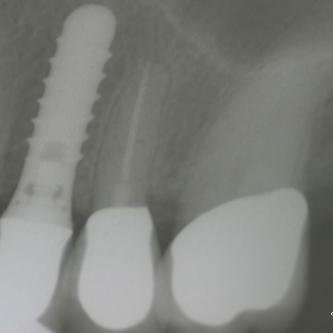

Exemple 14: Il est prévu de mettre un implant entre la molaire et prémolaire, mais le sinus se trouve à moins de 4 mm de la surface. Il faut donc relever le sinus avec une greffe d'os

Exemple 14: Un petit puits d'accès est créé afin d'atteindre le sinus, notez la membrane sinusienne.

Exemple 14: La fine membrane sinusienne est relevée, puis de l'os mélangé à de l'os artificiel est introduit dans la cavité.

Exemple 14: La cavité est maintenant remplie.

Exemple 14: Radiographie post chirurgicale.

Exemple 14: 6 mois plus tard, l'implant est introduit dans cette greffe sans toucher le sinus.